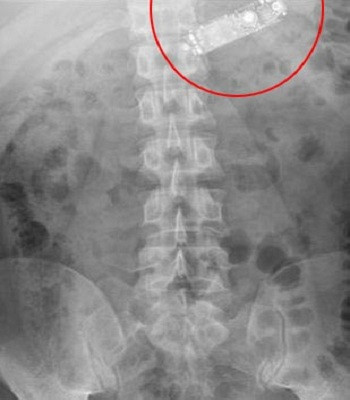

| Ảnh chụp X-quang chiếc điện thoại trong bụng bệnh nhân. Ảnh:Obinna Obinwa. |

Ban đầu, nhóm điều trị cố gắng lấy chiếc điện thoại ra theo phương pháp nội soi, sử dụng một thiết bị gắn camera đưa xuống cổ họng để gắp chiếc điện thoại ra. Theo Telegraph, đây là cách các bác sĩ lấy đồng xu, chìa khóa, nam châm và pin ra khỏi bụng bệnh nhân.

Tuy nhiên, khi cân nhắc kích thước của chiếc điện thoại và hướng nằm của nó, các bác sĩ quyết định từ bỏ kế hoạch trên do lo ngại khả năng làm tổn thương niêm mạc thực quản của bệnh nhân. Nhóm điều trị quyết định chuyển sang phương án dự phòng là mổ phần bụng trên của bệnh nhân và gắp chiếc điện thoại ra ngoài thành công.